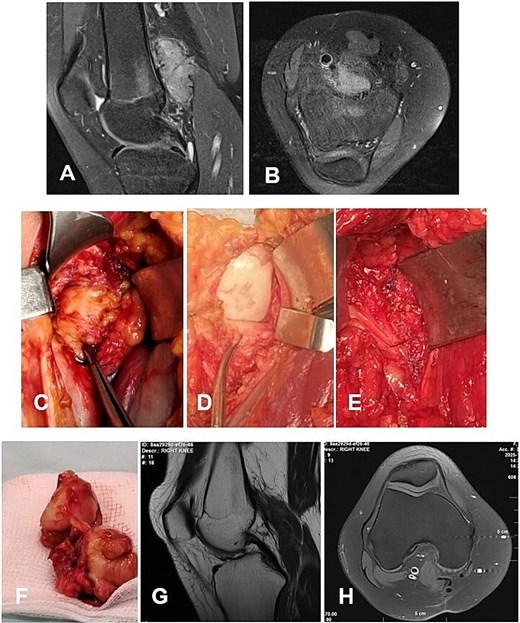

Case 1. (A and B) Preoperative T1 sagittal and axial MRI sequences with PD FS. (C and F) Macroscopic appearance of the pathological synovium before and after its excision. (D and E) The knee joint following synovectomy, demonstrating intact menisci and cruciate ligaments. Chondral lesions correspond to Outerbridge grade IV. (G and H) Postoperative 24 m. Sag and Ax MRI PD FS. No evidence of recurrence of the resected neoplasm was detected. Residual TGCT involvement persists within the lateral posterior femoral recesses. PD FS, proton density weighting with fat suppression; TSE, turbo spin echo.

Case 1

A 4-year-and-5-month-old child presented with a history of chronic synovitis of the right knee joint persisting for more than 2 years. Progressive limitation of motion was observed—a 15° flexion contracture, and maximum flexion limited to 75°. Magnetic resonance imaging (MRI) was concordant with the intraoperative findings, demonstrating diffuse involvement of both anterior and posterior recesses of the knee joint (Fig. 2A–C). A subtotal anterolateral synovectomy was performed. Intraoperatively, chondral defects corresponding to Outerbridge grade IV were identified (Fig. 2C–E). At 2-year follow-up, a substantial improvement in the range of motion was achieved (Table 1). Follow-up MRI demonstrated no evidence of local recurrence in the previously resected area of the neoplasm (Fig. 2G–H). A secondary synovectomy is planned to address residual synovial involvement within the posterior lateral femoral recess.